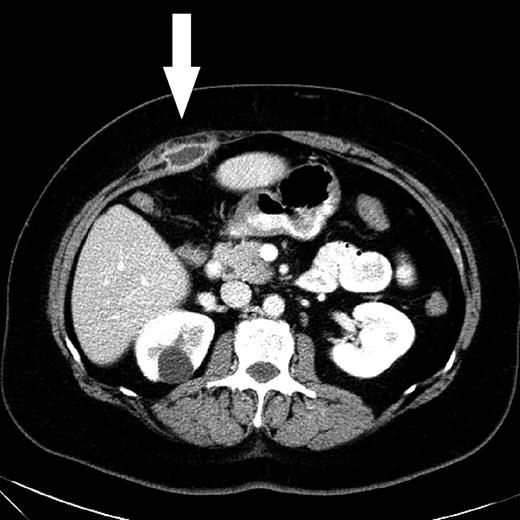

A control CT scan 3 months after the initial admission showed complete regression of the pelvic abscess. Furthermore, a 2 × 3 cm abdominal wall abscess was found behind the superior part of the right rectus abdominis muscle, equivalent to the port site where the perforated gall bladder was extracted 17 years earlier (Fig. 2). Ultrasonically guided biopsy showed acute inflammation and Escherichia coli.

CT scan shows an abscess with peripheral rim enhancement beneath the right rectus abdominis muscle. A simple cyst of the right kidney was a coincidental finding.